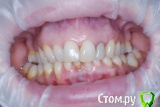

VVQW Опубликовано 25 октября, 2016 Поделиться Опубликовано 25 октября, 2016 (изменено) добрый день. Сложная ситуация. Более 10 лет назад ставили брекеты без анализов, диагностик, снимков и пр. Сейчас, что имееем, то и имеем. Большую проблему. Прикуса нет. Клиновидки из-за перегруза. Что можно сделать прошу совета и помощи. Обращалась за консультацией ко многим специалистам, мнения разнятся от слегка положительного, до просто критической ситуации. Последний профессор ортодонт вообще сказал - все вырвать и поставить протезы. УЖАС..... Может кто-нибудь из врачей даст совет... очень на Вас надеюсь. С уважением. Изменено 25 октября, 2016 пользователем VVQW Ссылка на комментарий

Brigita Опубликовано 26 октября, 2016 Поделиться Опубликовано 26 октября, 2016 Печальная картина...Но нужны хорошие фото - профиль, анфас, зубы в закрытом состоянии так, чтобы и боковая группа попала и фронтальная, снимки ТРГ, КТ.Зубы подвижны? Ссылка на комментарий

Brigita Опубликовано 6 декабря, 2016 Поделиться Опубликовано 6 декабря, 2016 (изменено) У Вас сложный случай, но лечение было бы возможным, если бы не резорбция корней верхней челюсти. Ортодонт принимая решение о лечении такого пациента должен понимать, что он берет на себя большую юридическую ответственность. Я думаю, все это Вам уже говорили. Ищите опытного врача и будьте готовы к вложению средств и потерям зубов... Скорее всего имплантация неизбежна и фронтального и частично бокового отдела.Сколько Вам лет? Изменено 6 декабря, 2016 пользователем Brigita Ссылка на комментарий